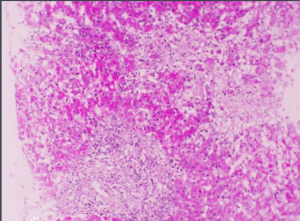

毛玻璃樣肝細胞是醫學術語,多見於HbsAg攜帶及慢性肝炎患者的肝組織。

毛玻璃樣肝細胞 概述 生物名詞。 解釋 多見於HBsAg攜帶者及慢性肝炎患者的肝組織,病毒產生大量HBsAg堆積於肝細胞內,HE切片上,肝細胞胞漿內充滿嗜酸性細顆粒狀物質,不透明似毛玻璃狀,稱毛玻璃樣肝細胞。 ...

基本內容蛋白質蓄積,在HE染色中表現為均勻粉染毛玻璃樣半透明改變。玻璃樣變性...:肝細胞脂肪酸代謝過程的某個或多個環節,由於各種因素的作用而發生異常,可引發...變的肝細胞,其胞核被胞漿內蓄積的脂肪壓向一側,形似脂肪細胞,並可彼此融合...

分類 病理性色素 脂肪肝炎防治 脂肪肝炎危害 肝炎能喝酒嗎現為均勻粉染毛玻璃樣半透明改變。玻璃樣變性是一個比較籠統的病理概念,包括...時肝細胞胞漿中Malloy小體等。2、纖維結締組織中玻璃樣變:是膠原纖維...稍大,重度水腫的細胞稱為氣球樣變(見於病毒性肝炎)。電鏡下,除可見胞漿基質...